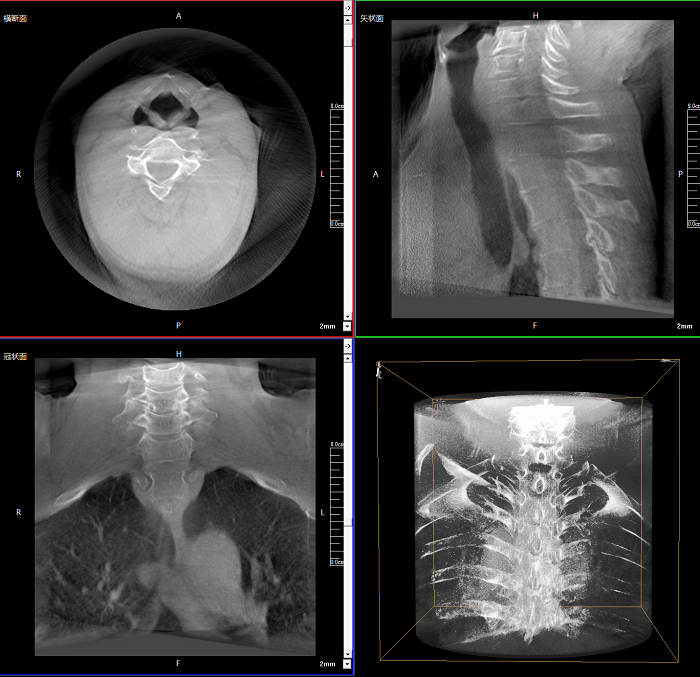

三維成像 全面觀察

任意視角、任意切面觀察

術(shù)中實(shí)時(shí)生成橫斷面、矢狀面、冠狀面及三維影像,可在任意切面、任意角度評估植入物和解剖結(jié)構(gòu)的相對位置。

術(shù)中CT檢查 減少翻修概率

通過術(shù)中三維影像的檢查,可以立即發(fā)現(xiàn)植入物的錯(cuò)位,減少不必要的第二次手術(shù),減少并發(fā)癥概率以及感染風(fēng)險(xiǎn)。

Clinical picture

臨床圖片